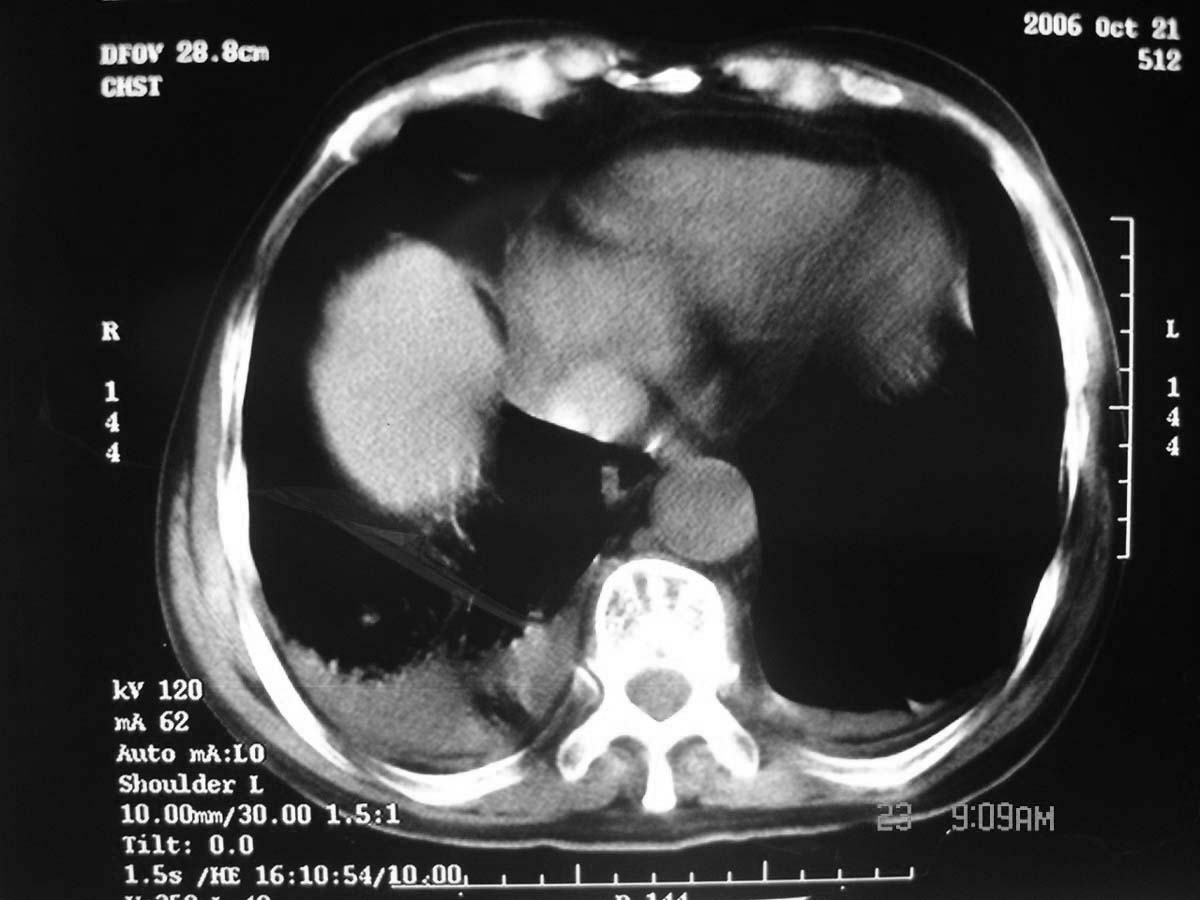

以下是引用守望可可西里在2006-11-23 14:33:00的发言:[br][br] 糖尿病病人很容易继发结核,病人又有双侧胸膜增厚、粘连、胸腔积液以及双上肺的斑片状、条索状影结核病灶影,以一元论考虑,右下肺病变首先考虑干酪性肺炎,可以正规抗炎治疗后复查,排除一般的肺炎。